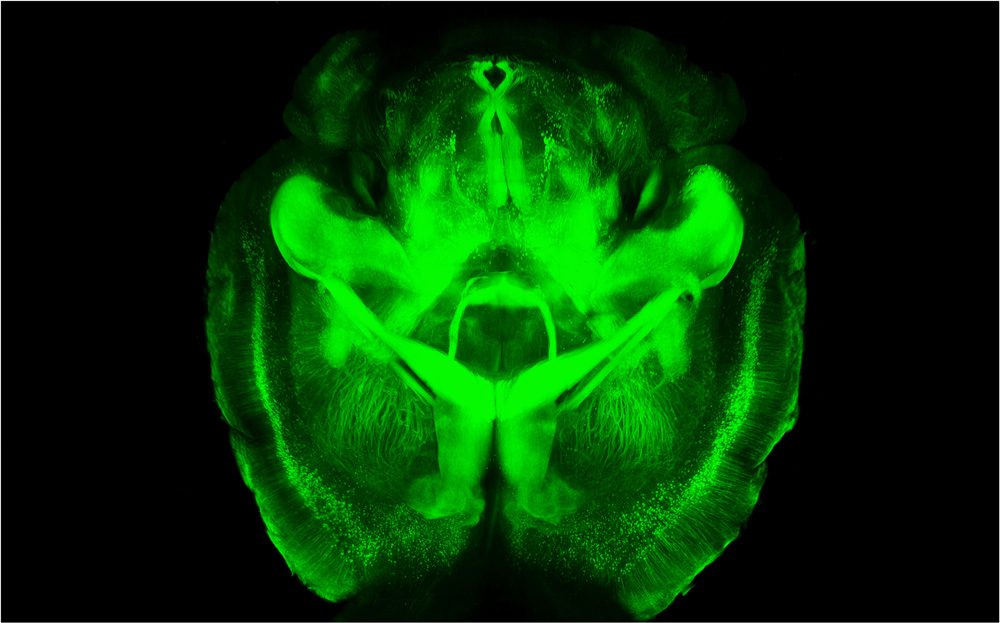

Flicker Of Hope For Alzheimer's? MIT Research Finds Light Helps Mouse Brains

That's pure fantasy, but it's the image that came to mind in response to the news — wild, but published in the prestigious journal Nature by star neuroscientists — that light flickering at a specific frequency could help the brain fight back the infamous amyloid plaques of Alzheimer's disease.

In mice, at least. Now the technique needs to be tested in humans, and a startup called Cognito Therapeutics is planning to do just that.